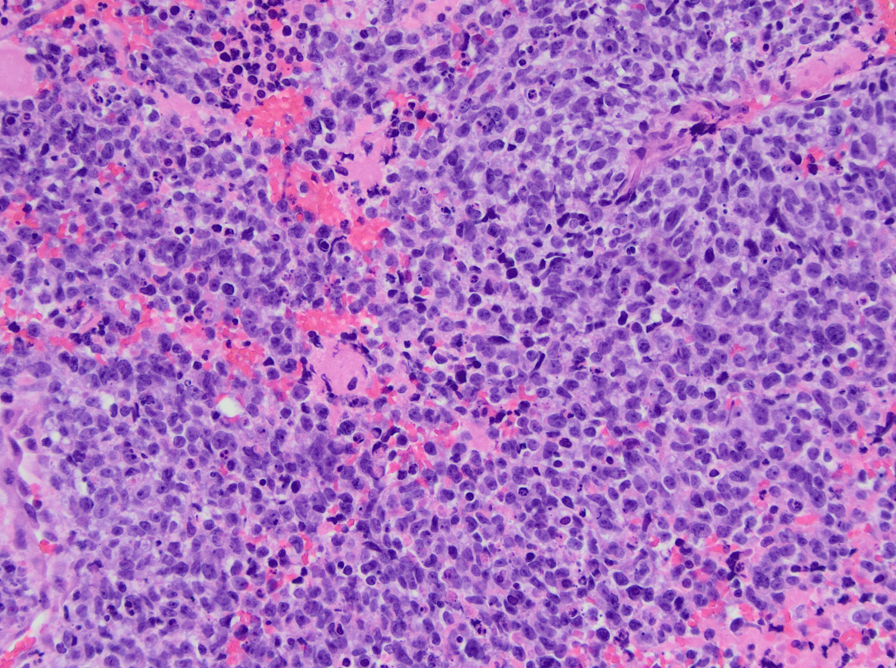

CIC-DUX4 rearranged sarcoma is a small blue round cell tumor resembling Ewing sarcoma. In addition to small blue round cells morphology, CIC rearranged sarcoma may also show focal areas of spindling and epithelioid/rhabdoid phenotype, with frequent myxoid stromal changes. Similar to Ewing sarcoma, it also shows strong cytoplasmic and membranous positivity of CD99. Patient age at presentation ranges from 6 to 70 years (mean age: 32 years). Most of the time it arises in the soft tissue of the trunk and extremities. Overall survival is worse than Ewing sacrcoma.